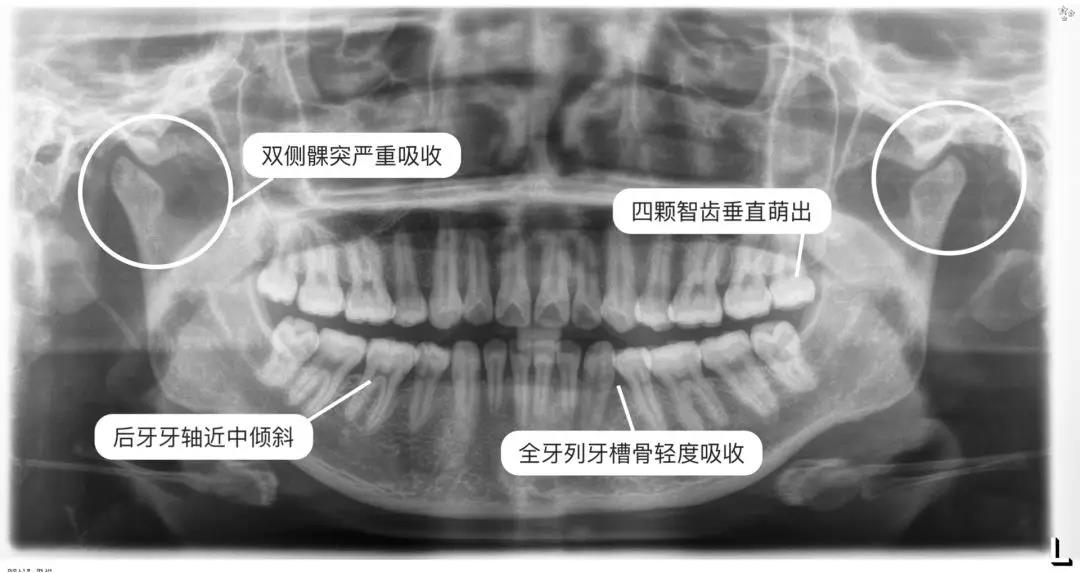

醫(yī)師通常會(huì)讓你拍兩張X光片

一張全景一張側(cè)位

通過(guò)這兩張片子

醫(yī)師能夠?qū)δ愕难例X、牙根、牙槽骨、頜骨

甚至關(guān)節(jié)等進(jìn)行判斷、數(shù)據(jù)分析

看到一些肉眼無(wú)法發(fā)現(xiàn)的問(wèn)題